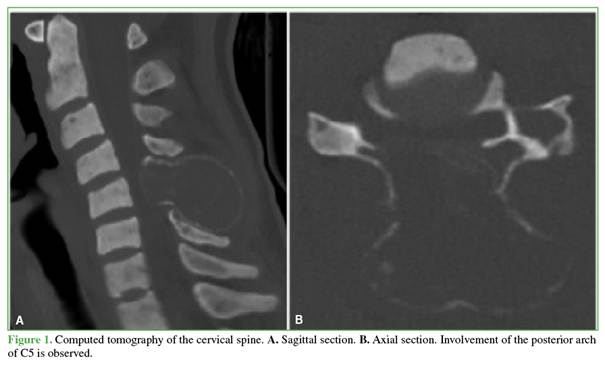

Plain radiographs and computed tomography of the cervical spine demonstrated a large osteolytic lesion with sclerotic margins involving the posterior arch of the fifth cervical vertebra, with extension into the adjacent soft tissues (Figure 1). Magnetic resonance imaging revealed severe spinal cord compression at the level of the fifth cervical vertebra (Figure 2).

Brown tumors typically appear on plain radiographs or computed tomography as lytic, multilobulated lesions that may or may not present peripheral sclerotic margins. On magnetic resonance imaging, these lesions are hypointense on T1-weighted sequences and hyperintense or isointense on T2-weighted sequences, with a tendency to invade adjacent tissues. Intravenous contrast administration usually results in lesion enhancement.7,8

In our patient, the lesion involved the entire posterior arch of C5 and extended not only into the paravertebral soft tissues but also into the posterior epidural space, producing significant spinal cord compression.